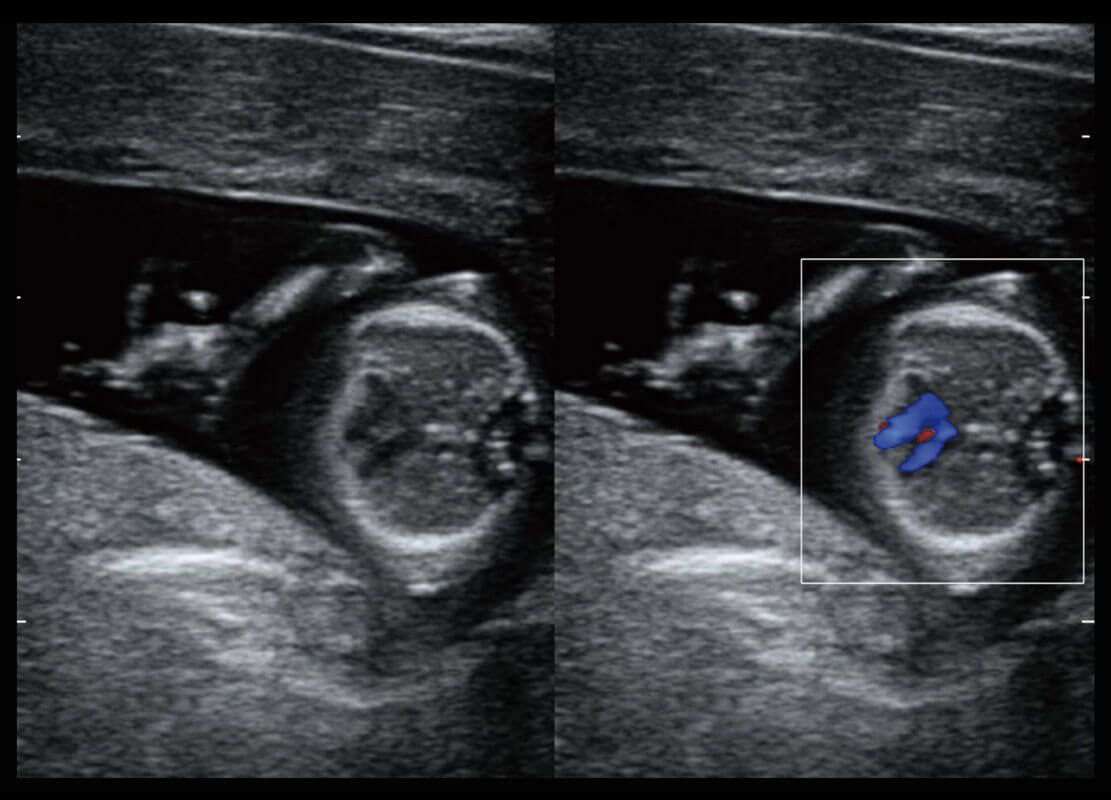

• 早孕-胎心

• 高分辨率容积成像-早孕胎儿

• 胎儿体循环

• 四腔心血流